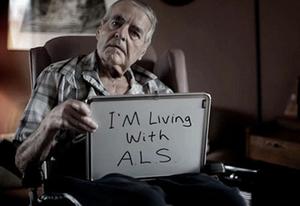

پایگاه خبری یزدفردا"یک متخصص مغز و اعصاب گفت: بیماری ALS علائم شناخته شدهای ندارد.

دکتر مهیار معتقد بیماری ALS را بیماری سیستم حرکتی دانست و اظهار کرد: ALS یک بیماری ضعف پیش رونده بوده که اعصاب حرکتی مرکزی و محیطی از جمله اندامها و عضلات حرکتی را تحت تاثیر قرار میدهد.

معتقد با بیان اینکه بیماران مبتلا به ALS با هوشیاری کامل و آگاهانه مسیر مرگ را طی میکنند، گفت: ابتلا به این بیماری در سنین 50 سال به بالا شایعتر است.

ALS یک بیماری عصبی پیشرونده است که سبب زوال تدریجی سلولهای عصبیای میشود که وظیفه کنترل حرکت ماهیچهها را به عهده دارند. با پیشرفت بیماری، افراد مبتلا رفتهرفته توانایی کنترل حرکت ماهیچههایشان را از دست میدهند. به عبارت دیگر، با مرور زمان فرد مبتلا آرامآرام تواناییهای حرکتی خود را از دست میدهد. البته توانایی تفکر و حافظه این افراد معمولا تحت تاثیر این بیماری قرار نمیگیرد.

دوره بیماری ALS

افراد مبتلا به ALS به طور میانگین سه تا پنج سال پس از بروز علائم بیماری زنده میمانند، اما این قانون کلی درباره همه مبتلایان صادق نیست. شواهد نشان میدهد برخی مبتلایان بیش از 5 سال و حتی به مدت 10 سال پس از بروز نخستین علائم نیز زنده ماندهاند و سپس جان خود را از دست دادهاند.